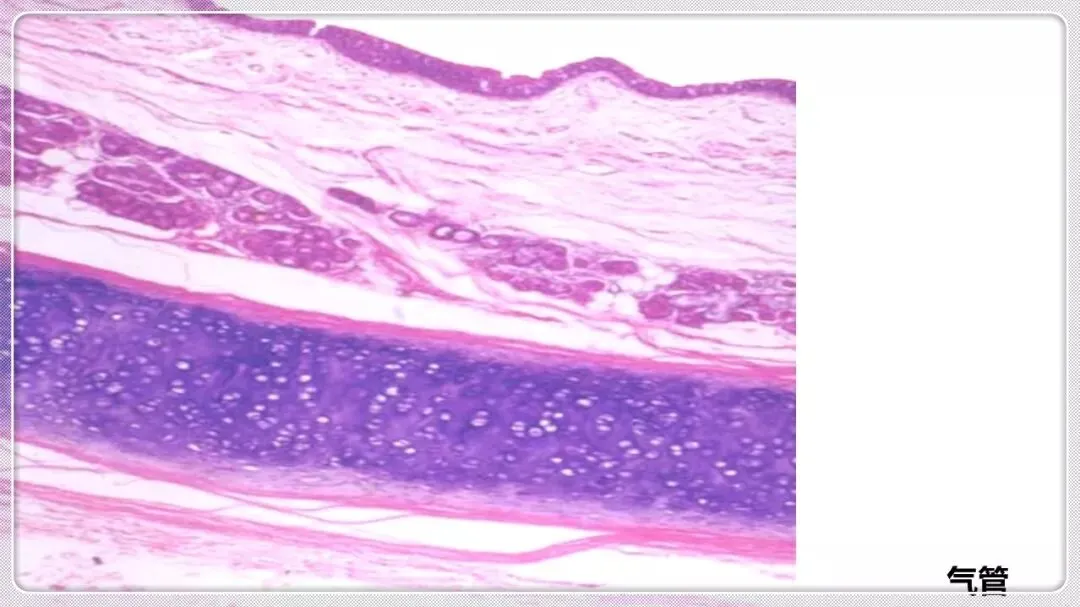

组织学与胚胎学笔记pdf【 常考图谱】

组织学与胚胎学 图谱